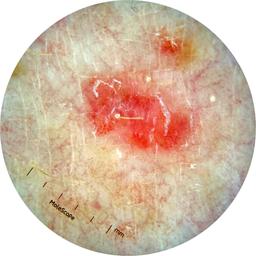

ISIC_7193897

IP_3751325

IL_3780211

Clinical

Field Value

acquisition_day 251

age_approx 65

anatom_site_1 Lower extremity

anatom_site_general lower extremity

concomitant_biopsy False

diagnosis_1 Benign

diagnosis_confirm_type single image expert consensus

family_hx_mm False

image_manipulation instrument only

image_type dermoscopic

lesion_id IL_3780211

patient_id IP_3751325

personal_hx_mm True

sex female